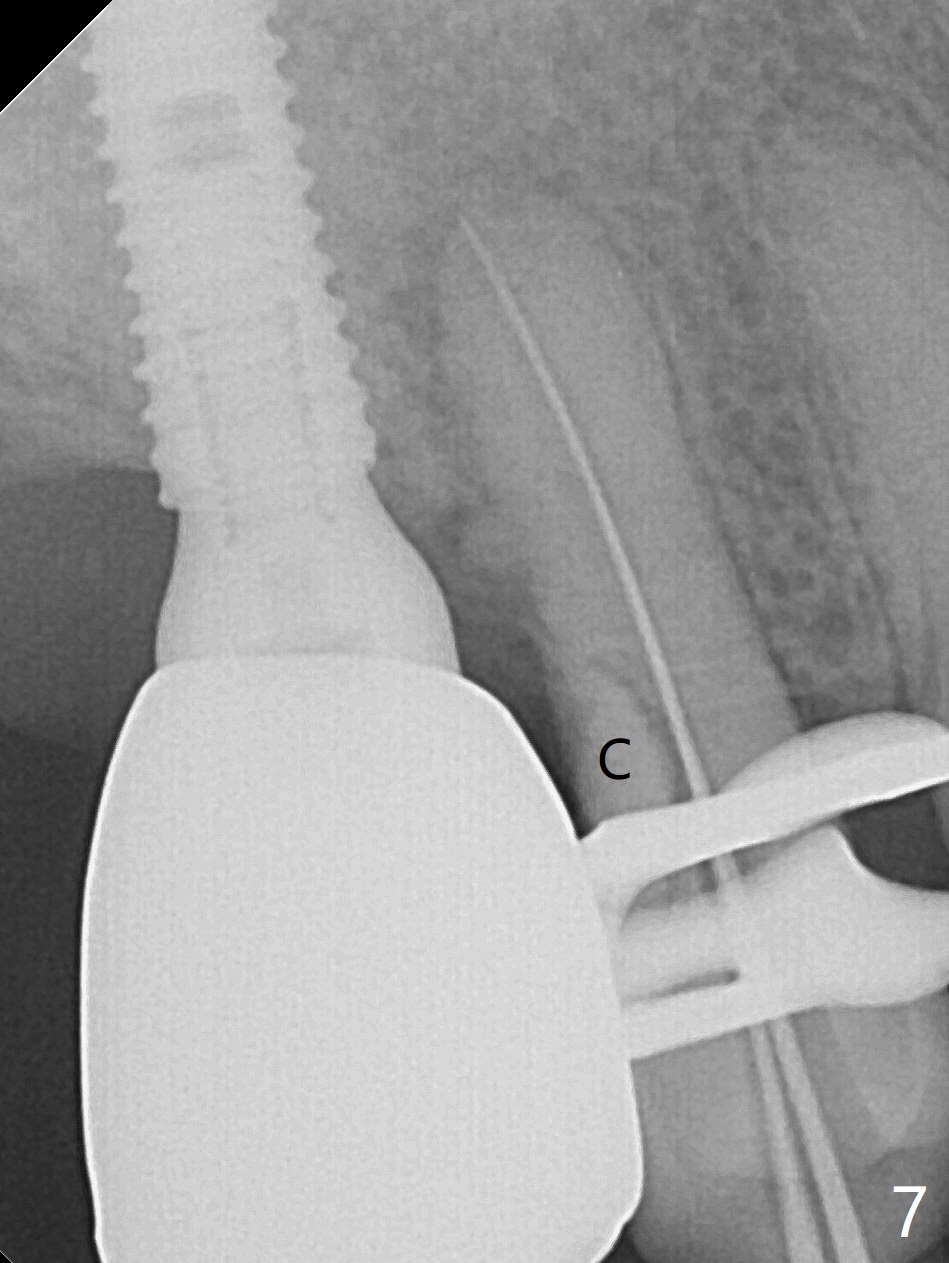

Since the ridge crest at #3 is narrow, Tatum bone scalpels are used to get access and initiate bone expansion, followed by bone blades and RT 2. It seems that the osteotomy starts mesially; bone height being increased (Fig.1). When the apical end of the osteotomy tilts mesially, more bone height is obtained. Drills are alternatively applied because of the hard bone (Fig.2). A 4x13 mm UF implant is placed initially with the distal threads unburied (Fig.3, >50 Ncm). With further seating of the implant, a 5.5x5(4) mm abutment is used (Fig.4), which closes the access. No suture is warranted. An immediate provisional is fabricated for the patient's comfort and psychological effect. In fact, the abutment cuff changes to 5 mm prior to temporarization. There appears no bone loss <4 months postop (Fig.5). Pulpitis develops at #4 due to DO caries 1 year 5 months post cementation (Fig.6 *). The crown at #3 is removed for easy and conservative distal carious removal and Cavit temporary restoration to prevent sodium hypochlorite leakage. Then occlusal access is made for pulpotomy. When RCT finishes, no crown will be made, but occlusal reduction is required. The patient returns for RCT 1 month later (Fig.7,8). Cavit remains in place (Fig.7 C). Although 2 threads are exposed distal (Fig.8 arrow), there is no sign or symptom of periimplantitis, which may be related to the thick gingiva (arrowhead). Return to Upper Molar Immediate Implant, IBS, #14 (Tissue Punch) Xin Wei, DDS, PhD, MS 1st edition 08/25/2017, last revision 09/08/2019